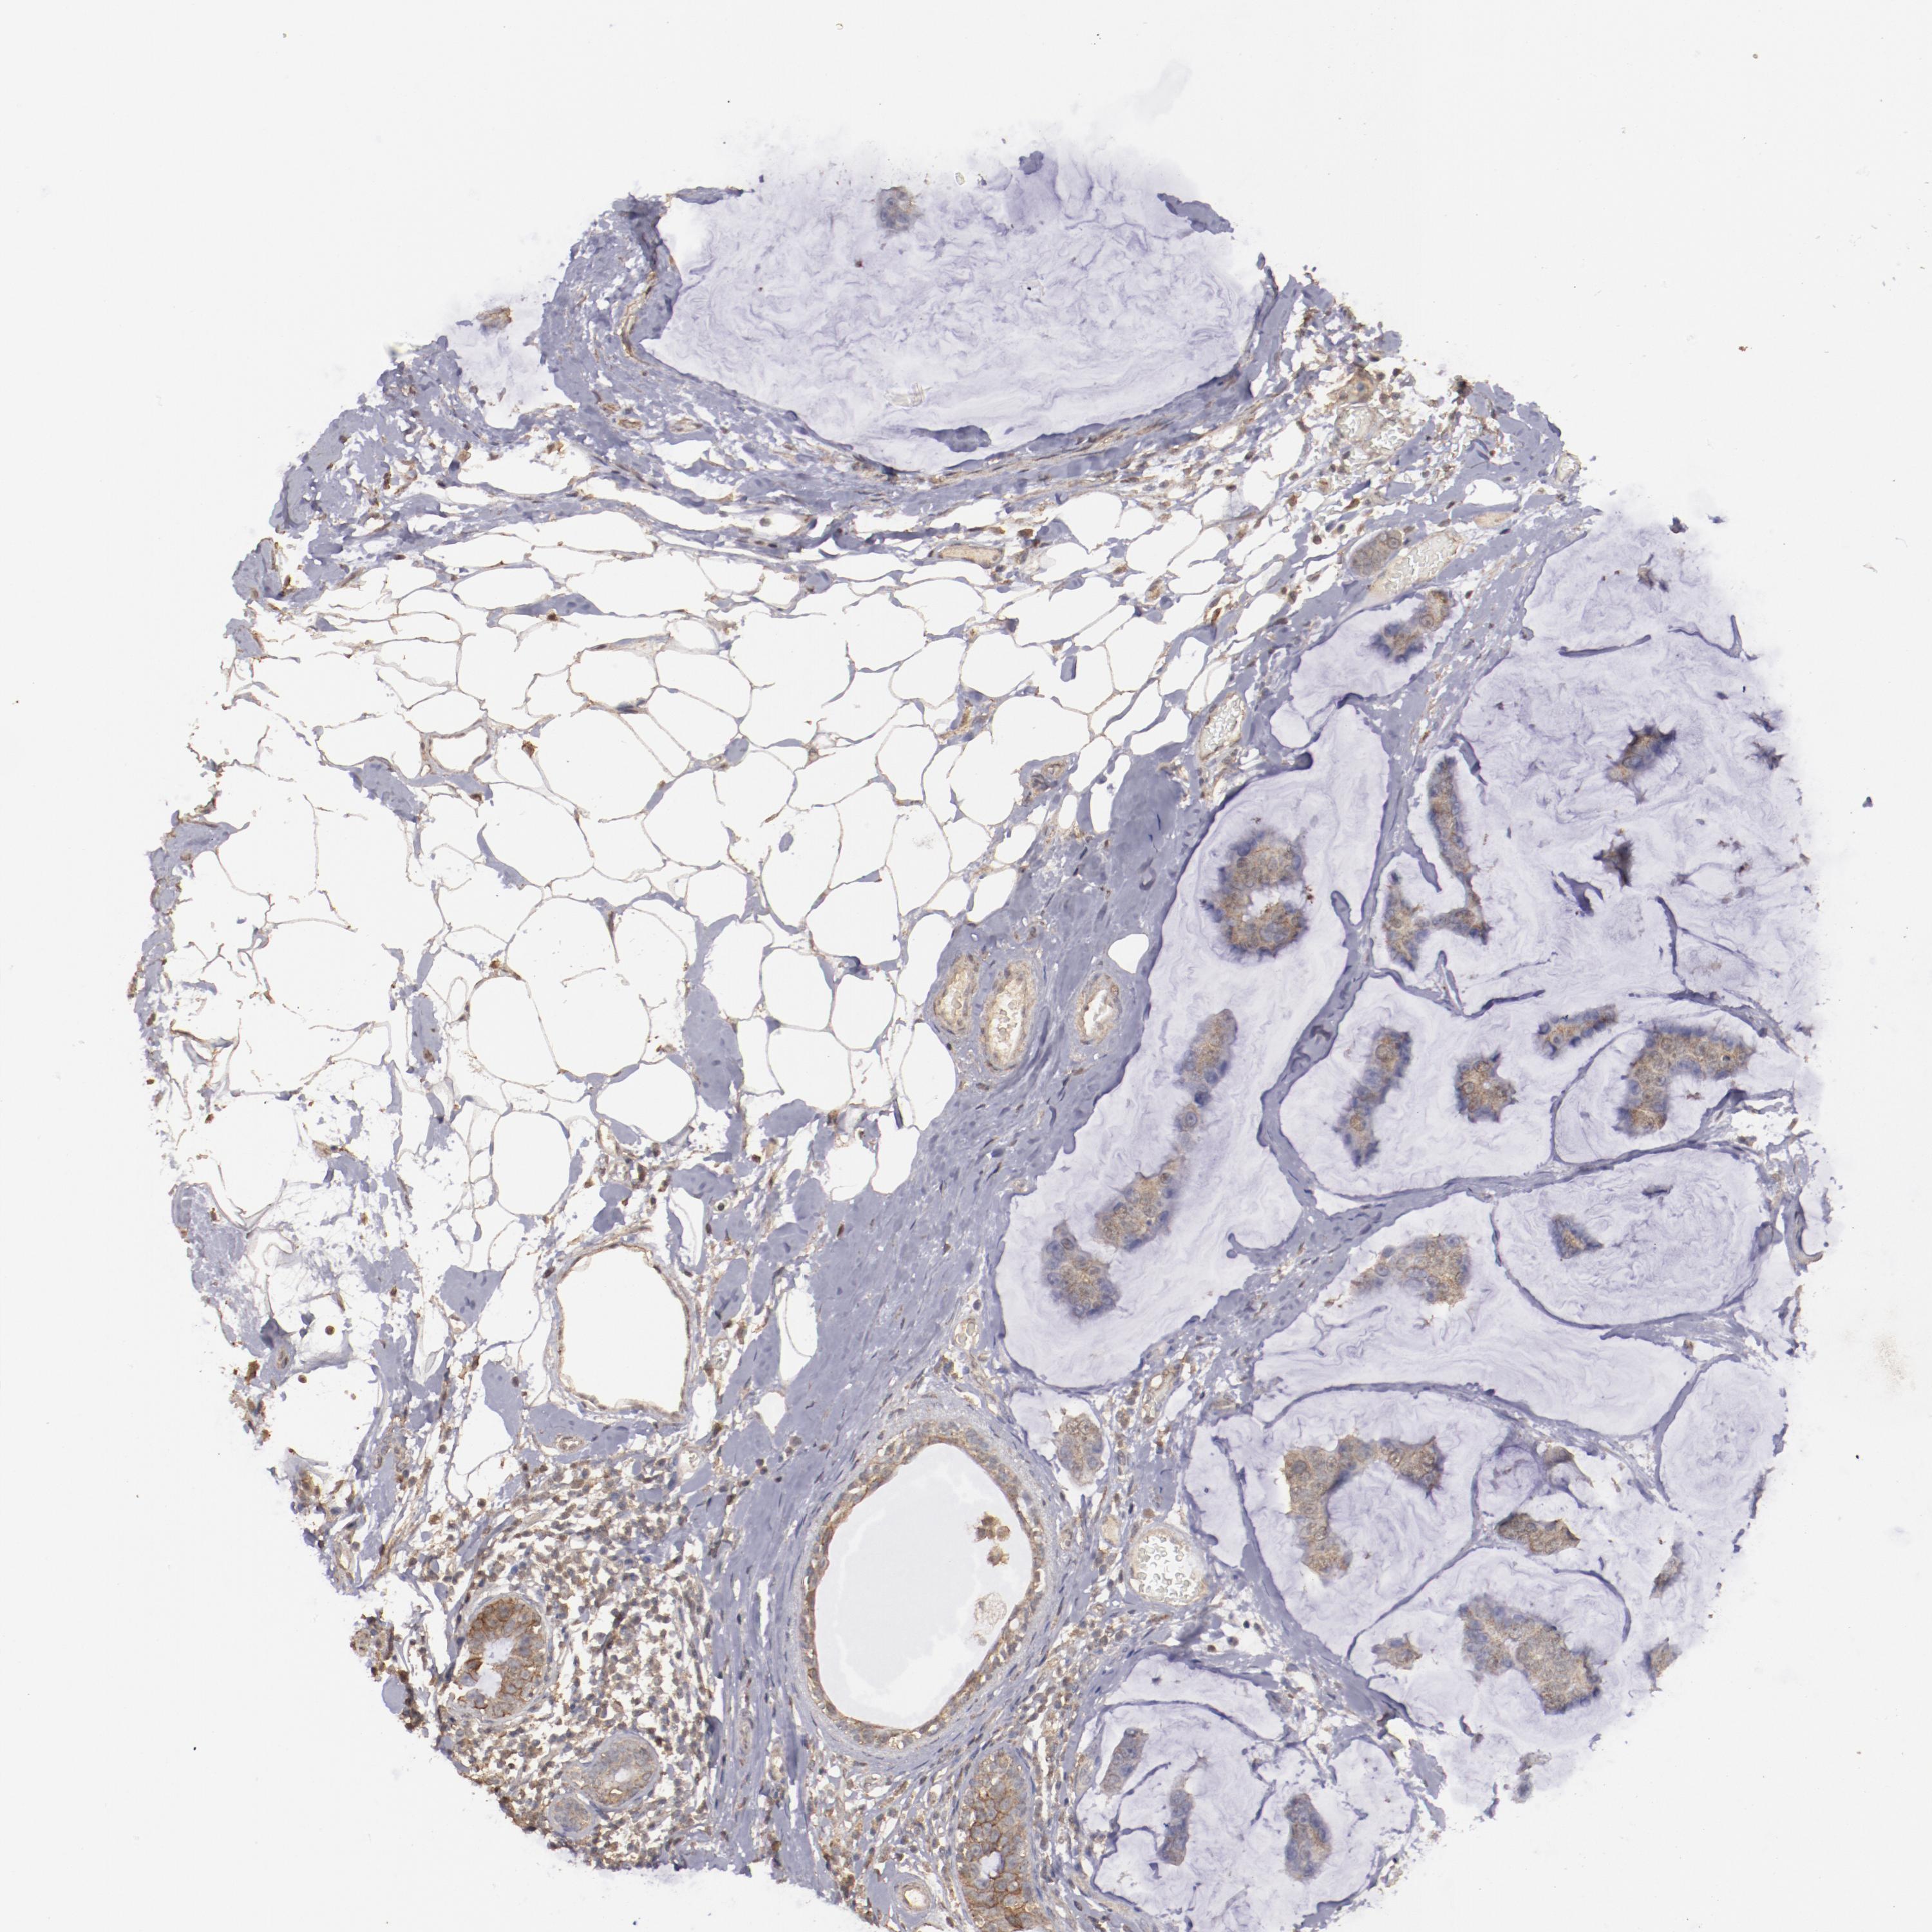

CANCER BREAST CANCER Show tissue menu

BRCA TCGA BRCA VALIDATION PROTEIN EXPRESSION